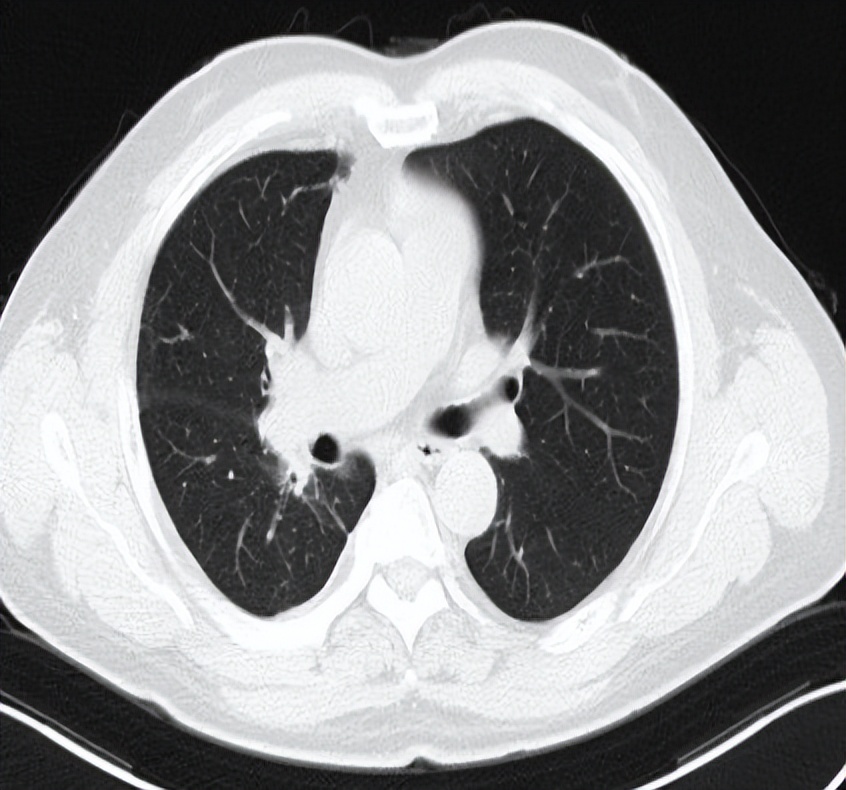

2022-3-6入院复查胸部CT见右肺上叶病灶增大,评价为病情进(PD),予以行胸部SBRT治疗,总剂量40Gy/8Fx。